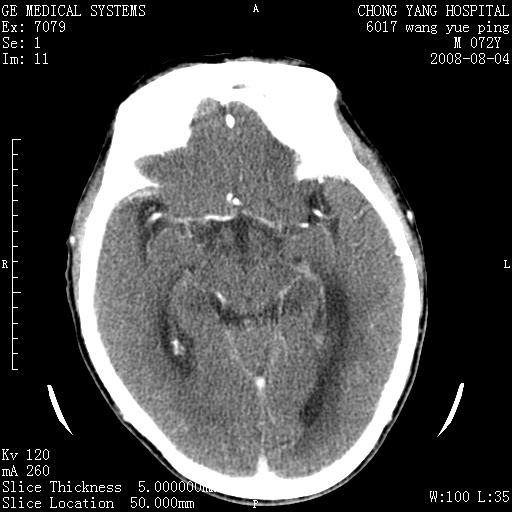

标题: CT14987:M72Y,头痛头昏,BP220/110. [打印本页]

标题: CT14987:M72Y,头痛头昏,BP220/110.

1)考虑左侧小脑脑梗塞。2)脑白质病。3)脑萎缩。4)双侧鼻腔新生物(息肉?)并阻塞性副鼻窦炎。

1.左侧小脑大面积梗塞;2.左侧基底节区腔梗;3.白质疏松;4.脑萎缩;5.慢性副鼻窦炎

小脑左侧病灶呈扇形分布,增强后未见明显瘤体样节结影,病变区未见强化。

支持:左侧小脑脑梗塞梗塞表现

另:脑白质病。脑萎缩。双侧鼻腔新生物(息肉?)并阻塞性副鼻窦炎。

1)考虑左侧小脑脑梗塞,建议治疗后复查除外其他,左基底节区腔隙性脑梗塞2)脑白质变性3)脑萎缩。4)双侧鼻腔新生物(息肉?)并阻塞性副鼻窦炎。